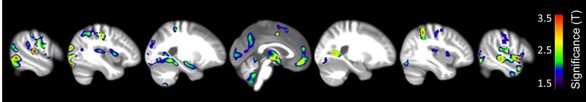

Áreas onde a correlação entre substância cinzenta e idade era significantemente diferente entre pessoas que meditavam e que não meditavam.